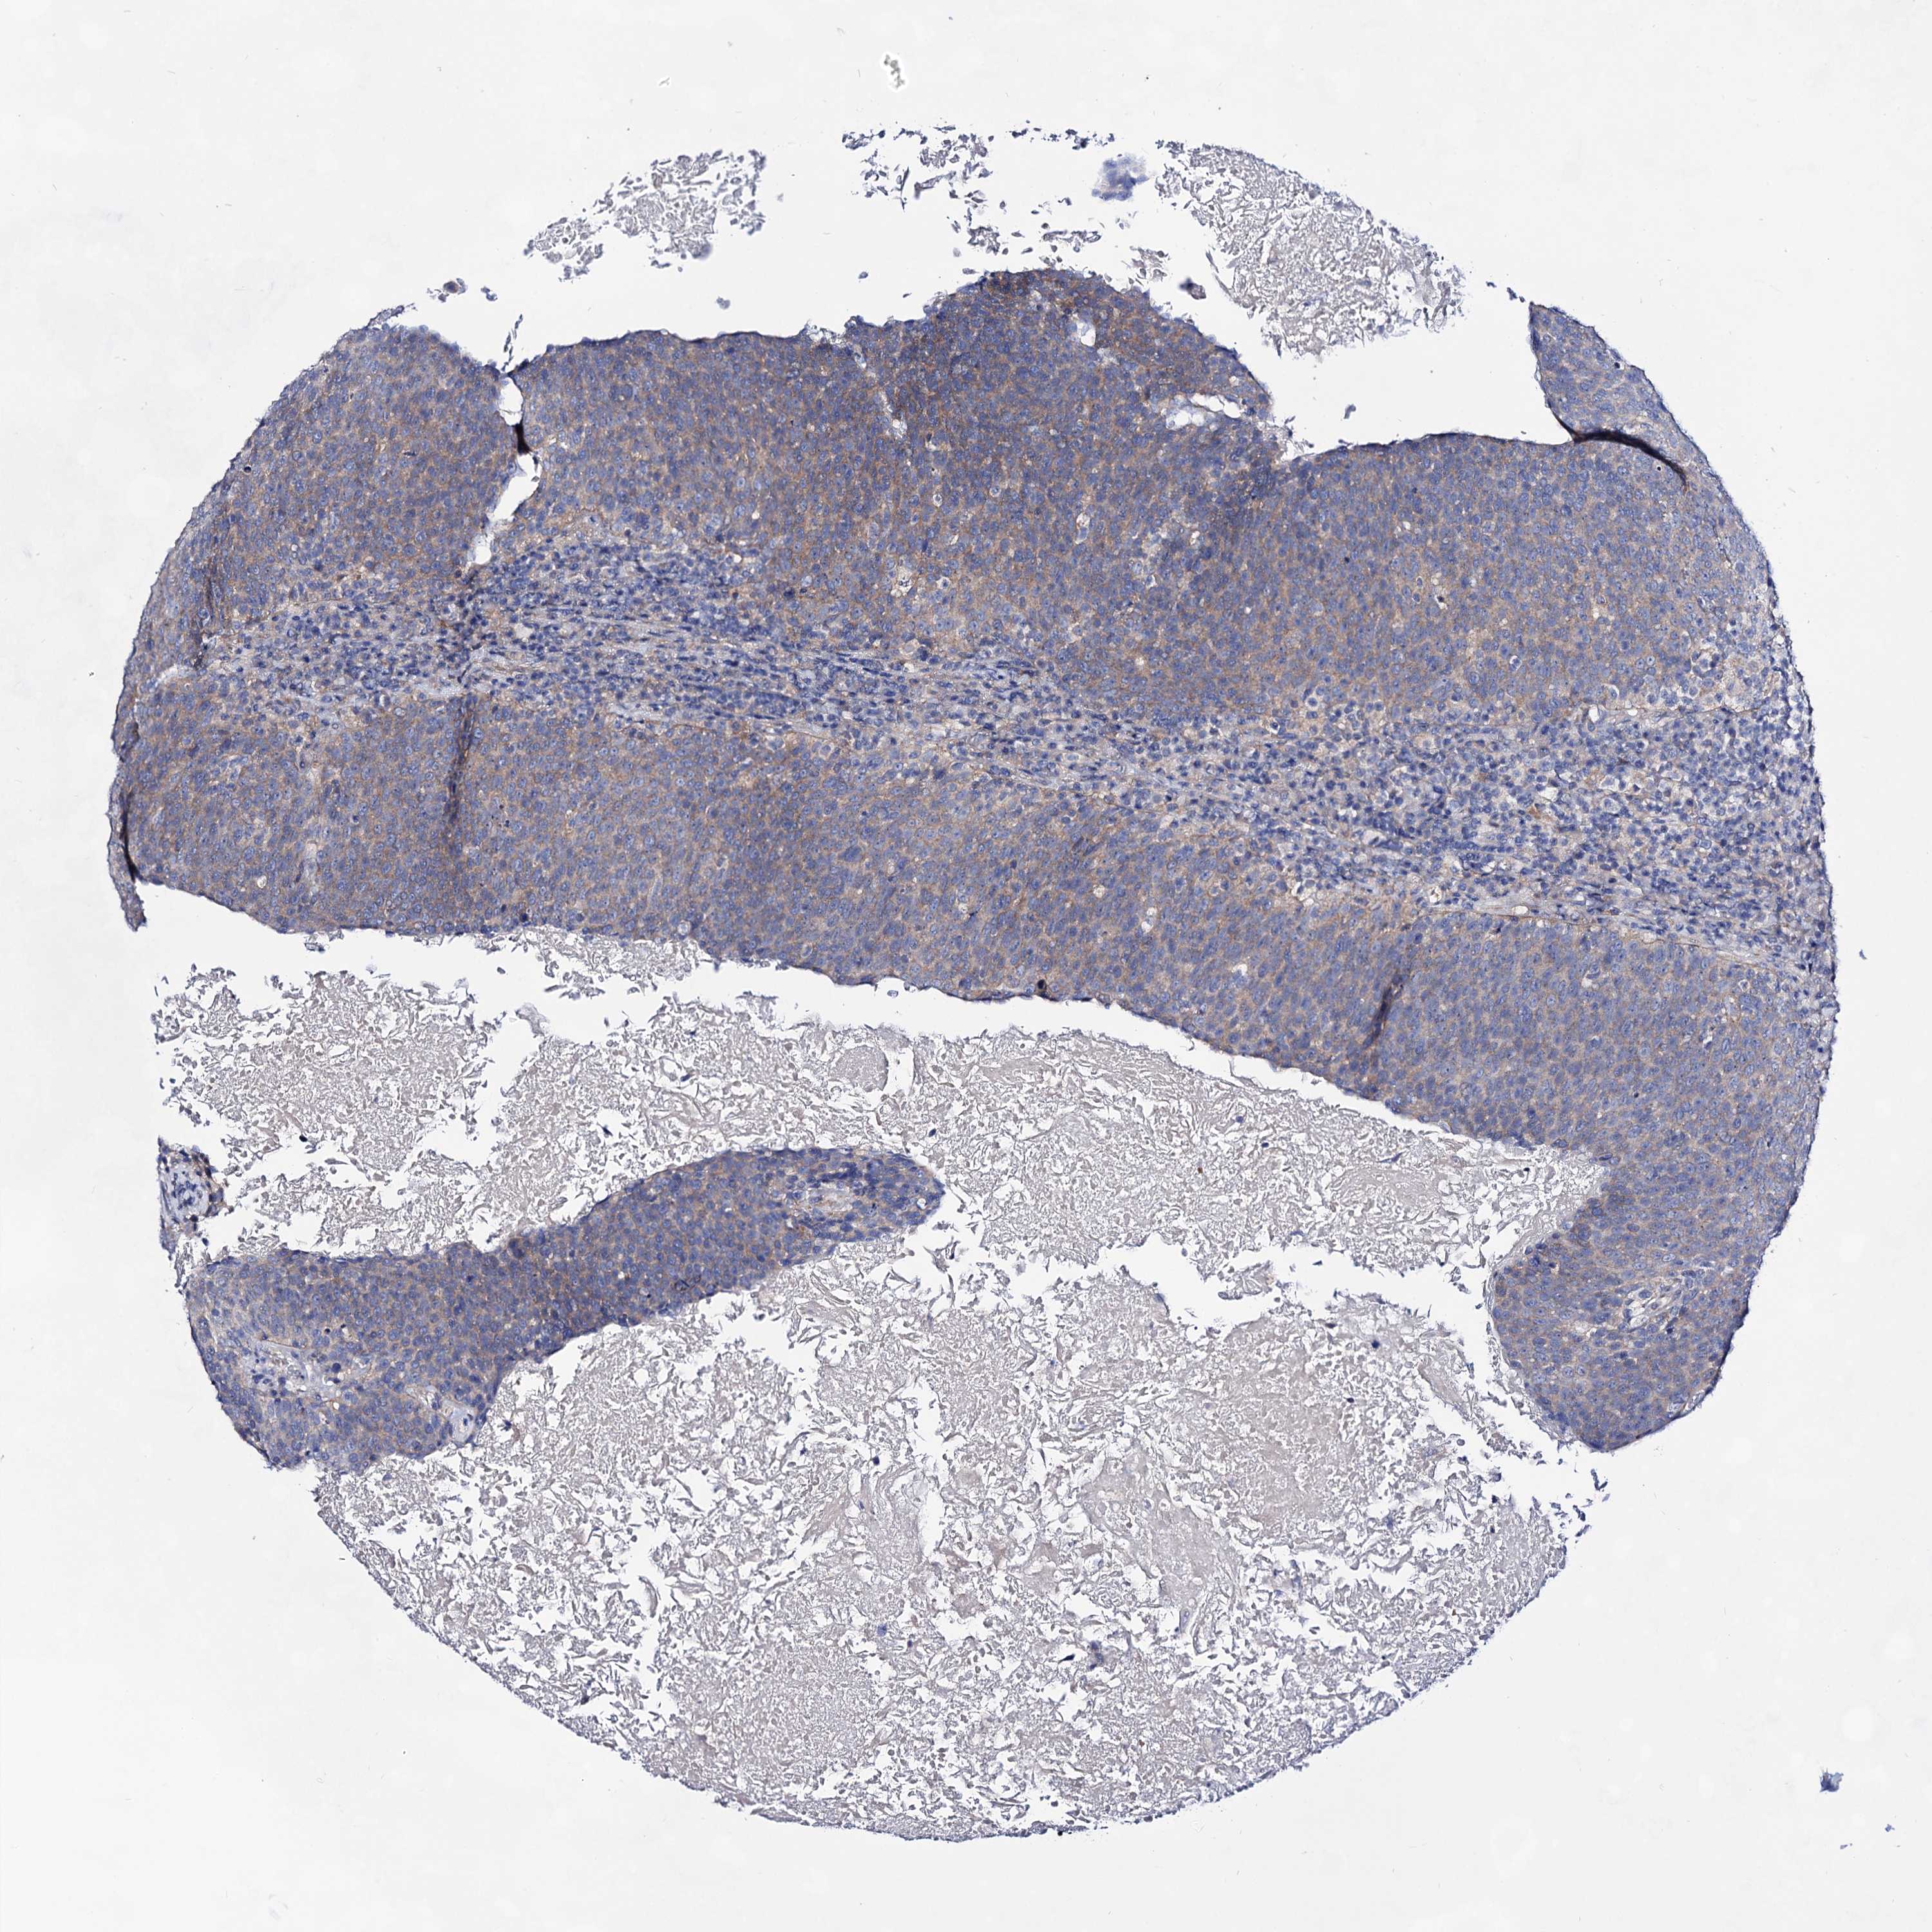

HEAD AND NECK CANCER - Protein expressioni

A mouse-over function shows sample information and annotation data. Click on an image to view it in a full screen mode. Samples can be filtered based on level of antibody staining by selecting one or several of the following categories: high, medium, low and not detected. The assay and annotation is described here.

Antibody stainingi

Antibody staining in the annotated cell types in the current human tissue is reported as not detected, low, medium, or high, based on conventional immunohistochemistry profiling in selected tissues. This score is based on the combination of the staining intensity and fraction of stained cells.

Each image is clickable and will lead to virtual microscopy that enables deeper exploration of all samples and also displays staining intensity scores, fraction scores and subcellular localization as well as patient and tissue information for each sample.

Antibody HPA024299

Antibody CAB033821

Antibody CAB037333

Staining

High

Medium

Low

Not detected

Intensity

Strong

Moderate

Weak

Negative

Quantity

>75%

75%-25%

<25%

None

Location

Nuclear

Cytoplasmic/membranous

Cytoplasmic/membranous,nuclear

Squamous cell carcinoma, NOS

Squamous cell carcinoma, metastatic, NOS

Adenocarcinoma, NOS

Adenocarcinoma, metastatic, NOS